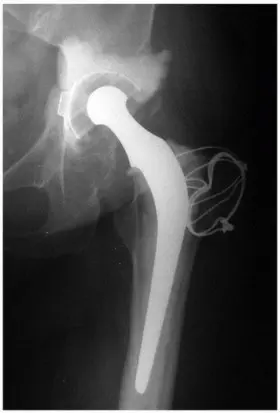

FIGURE 4-1 Classic Charnley low-friction arthroplasty performed with trochanteric osteotomy fixed in the lateralized “first position.” This, along with medialization of the acetabular component, favorably influences the abductor moment arm and increases stability against dislocation. (Radiograph courtesy of David K. Halley, MD.)